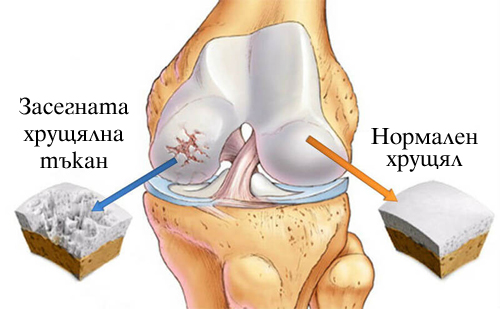

Доставеният колаген тип II с Колаген 500 мг с Л-лизин и Витамин C улеснява диференциацията на остеобластите (основните костно образуващи структури), намалява болката в ставите (особено по време на тренировка) и подобрява състоянията, свързани с болки, причинени от дегенерация на ставите, когато се приема редовно.

Collagen with Lysine + Vitamin C на страхотна цена се бори с причините за процеса на стареене, като може не само да намали скоростта му, а и да го стопира. Допринася за гъвкавостта на ставите, предотвратява изтъняването на хрущяла, редуцира болката и възпалението, укрепва състоянието на целия организъм. Collagen на таблетки действа за възстановяването и укрепването на съединителната тъкан, особено след травми, следоперативен период, дегенеративни заболявания на опорно-двигателния апарат, когато тялото трябва най-бързо да възвърне целостта му. От неговата патология зависи развитието на много хронични заболявания. Хранителната добавка съдейства за подобряване на дългосрочния комфорт, както и подвижност на опоно-двигателния апарат.